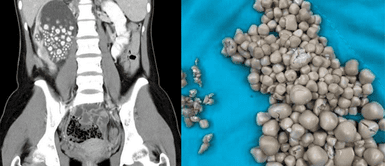

Una joven de 20 años fue sometida a una cirugía de emergencia en Taiwán para remover más de 300 cálculos renales, luego de ser ingresada al hospital con fiebre y fuertes dolores de espalda. El sorprendente caso ocurrió en el Centro Médico Chi Mei, en la ciudad de Tainan, donde los médicos detectaron una gran cantidad de piedras en los riñones de la paciente a través de una ecografía.

La paciente, identificada como Xiao Yu, presentó un cuadro alarmante de riñones inflamados llenos de pequeños cálculos, los cuales fueron descritos por los especialistas como "bollos al vapor". Tras realizarse una tomografía computarizada, los cálculos fueron identificados con tamaños que variaban entre 5 mm y 2 cm, mientras que los análisis de sangre mostraron un aumento en el recuento de glóbulos blancos, lo que indicaba una infección asociada.